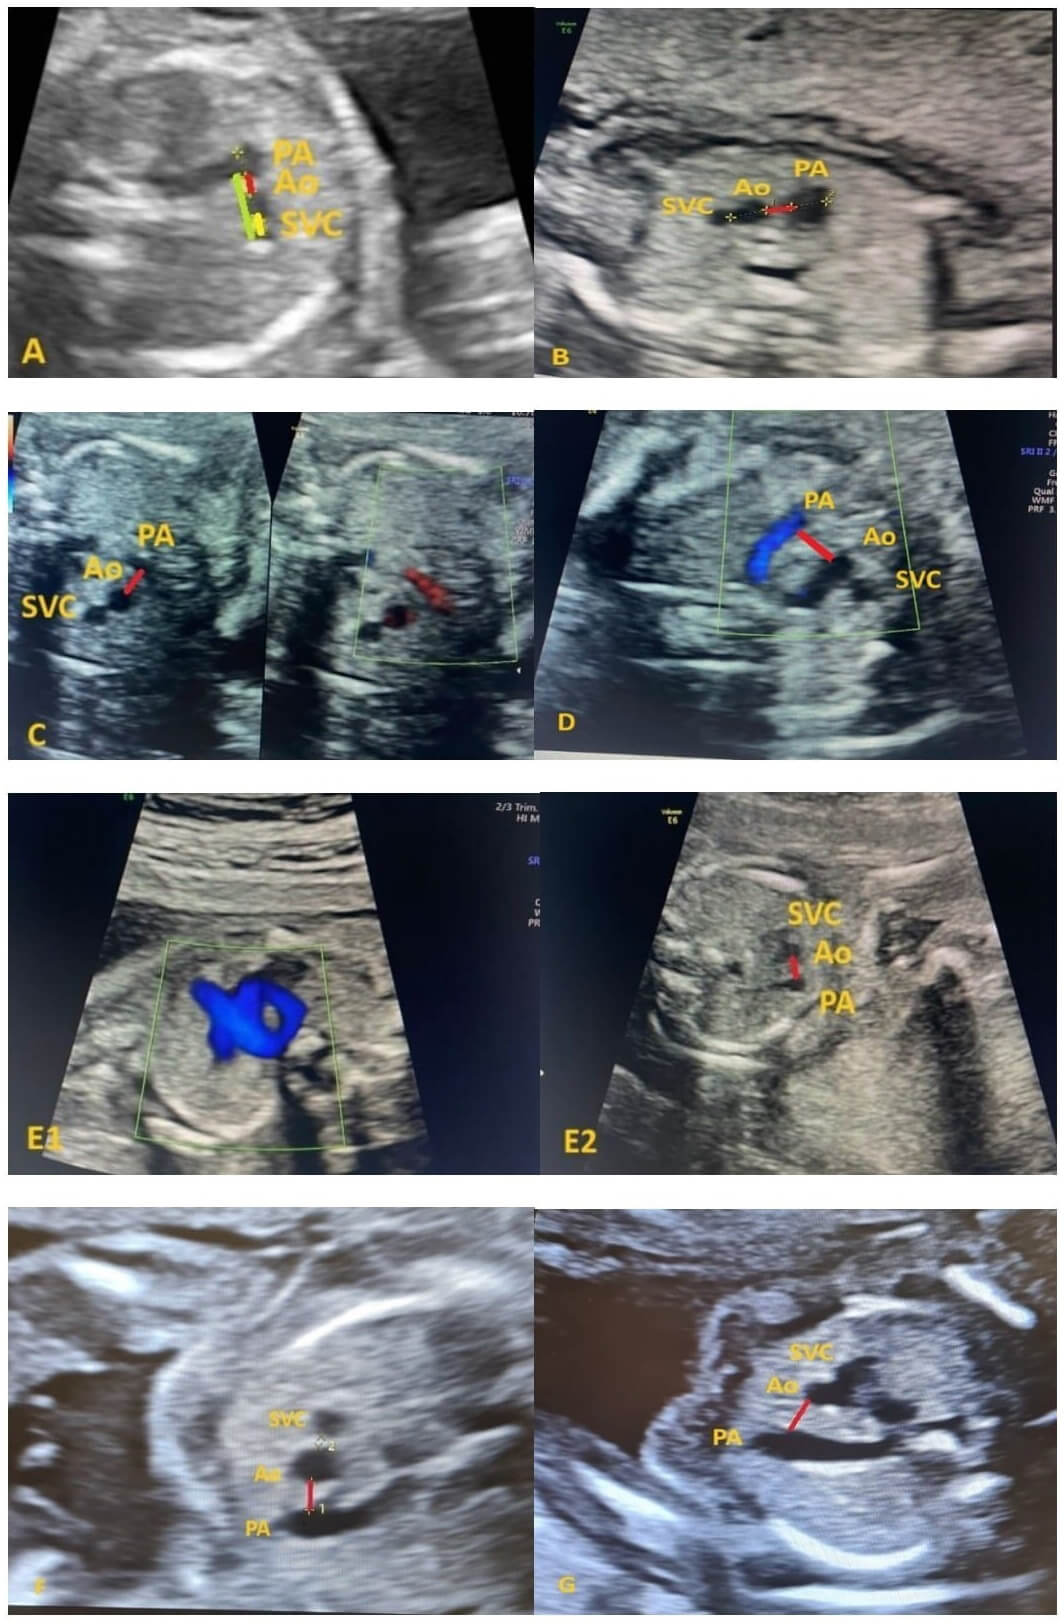

In this study, assessments were performed using the three-vessel view obtained during routine fetal echocardiographic examination. The image was zoomed to fill approximately two-thirds of the screen. The Doppler mode was not used. Images of the pulmonary artery (PA), aorta (Ao), and superior vena cava (SVC) were acquired. Distances between vessels were evaluated as the shortest distance between two vessels, and measurements were taken from lumen to lumen. Measurements were taken electronically from images. A sample image with color enhancement was provided in Fig. 1A.

Fig. 1.

Representation of 3-vessel views in the fetal echocardiographic examination of all cases included in the study. (A) Demonstration of the distance measurements between vessels in the three-vessel view during fetal echocardiography in a fetus without anomalies [13]. (B) Case 1, a 20+1 weeks fetus with a RAA anomaly. (C) Case 2, 20+2 weeks fetus with a RAA anomaly. (D) Case 3, 19+2 weeks fetus with a RAA anomaly. (E1) Case 4, 20+2 weeks fetus with a DAA anomaly shown with color Doppler. (E2) Case 4, 20+2 weeks fetus with a DAA anomaly shown in the three-vessel view. (F) Case 5, 20+5 weeks fetus with a RAA anomaly. (G) Case 6, 19+1 weeks fetus with a RAA anomaly. PA, pulmonary artery diameter; Ao, aortic diameter; SVC, vena cava superior diameter; RAA, right aortic arch; DAA, double aortic arch. Red line, distance between PA and Ao; yellow line, distance between Ao and SVC; green line, distance between PA and SVC.

The distances between the main PA–Ao, between the Ao–SVC, and between the main PA and the SVC were measured within the vascular lumen (PA–SVC) in the 3-vessel view (Fig. 1A) [13].

The gestational ages of the six fetuses included in the study ranged from 19+1 to 20+5 weeks. In five of the six fetuses, a RAA anomaly was present (Fig. 1B–D,F,G), whereas one fetus had a DAA anomaly (Fig. 1E). The measurements of the PA diameters ranged from –1 SD to +2 SD, while the Ao diameters ranged from –1 SD to +3 SD. The PA–Ao distance was found to be above +3 SD in five out of the six cases, while in only one fetus, it was evaluated between +1 SD and +2 SD. The PA–SVC distance was above +3 SD in four of the six fetuses. The remaining two fetuses were evaluated between 0 to +1 SD and +2 SD to +3 SD. In the Ao–SVC distance, only 2 fetuses had values below –3 SD, while no significant changes were observed in the other fetuses (Table 1).

Fig. 1A shows a demonstrative representation of the measurements for a fetus without any cardiac anomalies, whereas the subsequent measurements are presented as images specific to each case.